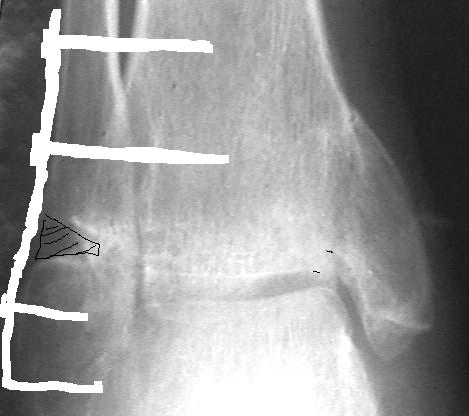

Коллеги! Я думаю надо плясать от возраста, профессии, объёма движений и интенсивности болевого синдрома. Ничего подобного не прозвучало... Имеет место подвывих стопы кнутри, никем не отмеченный! Оно конечно варус лучше, чем вальгус, но в данном случае принципиально его устранение (если оперировать конечно). Если оперировать, то предлагаю:

1. Остеотомию и низведение внутренней лодыжки. Фиксация винтом или пучком спиц.

2. Остеотомию наружной лодыжки и фиксация компрессирующим винтом (при необходимости дополнить аутокостью). Винт должен быть достаточно длинным дабы соблюдать ось!

Данными манипуляциями устраняем подвывих стопы, гиперпрессию дельтовидной связки и пытаемся устранить ложный сустав наружной лодыжки (существование которого весьма сомнительно). Но судя по снимкам щель сустава уже возможно заполнена рубцом, либо капсула сильно рубцово изменена и нормализация движений в п/о периоде сомнительна. Так, что попробовать конечно можно, но нужно ли.